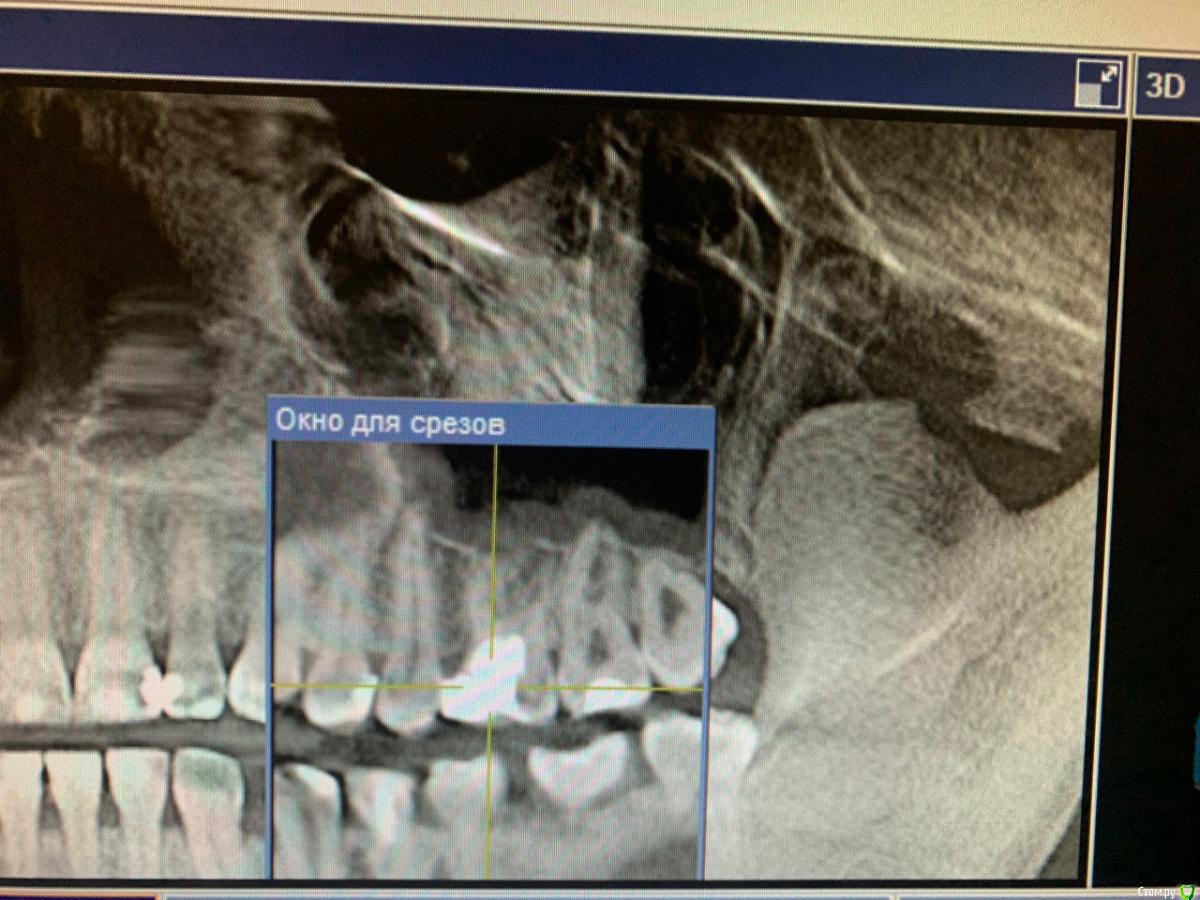

Nataly45 Опубликовано 8 октября, 2019 Поделиться Опубликовано 8 октября, 2019 Добрый вечер, мне очень нужен Ваш совет. Сразу скажу я была в 2 клиниках. и Завтра записала к члх на удаление этой 6 ки. Но очень сомневаюсь В пятницу вечером больно кусать стало, в субботу немного болело(пошла сразу к врачу сделали снимок всей челюсти) сказали надо именно удалять и именно у члх, прописали антибиотик и обезбол. Купила ,начала пить сразу. В воскресенье началась к вечеру приличная боль , о еде и речи не могло быть даже челюсть сомкнуть не могла. В понедельник,чтобы перепроверить первый диагноз удаление пошла в клинику другую,показала им снимок. Там врач предложила попробовать сохранить свой зуб играясь с лекарством,те каждые 2 недели разное лекарство в зуб закладывать,а потом резекцию. Дело это не быстрое но может сохраним зуб и поможет. Но гарантий никаких ,если что удалим. в понедельник началась мега адовая боль,ничего не помогала,звоню первому врачу,сменили антибиотик и обезбол и о чудо, мне стало легче и отлегло. Сегодня целый день не болит. но кусать больно . сказали еще что под зубом киста.Что делать? удалять или попробовать свой сохранить. Спасибо Ссылка на комментарий